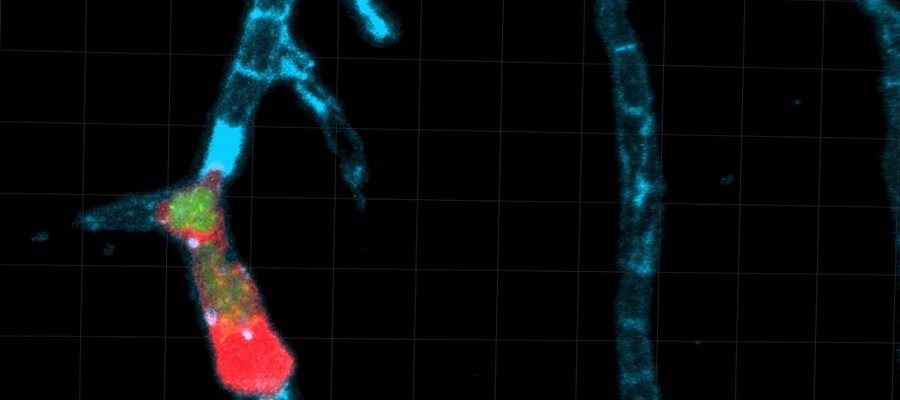

Studien, som är publicerad i Nature Communications, visar hur parasiten manipulerar infekterade immunceller så att de klibbar fast i hjärnans kärlväggar så att parasiten kan ta sig in i hjärnan på bara några timmar.

Med hjälp av klisterliknande molekyler, ICAM-1 och CD18, klibbar de infekterade immuncellerna fast vid kärlväggen inne i hjärnan.

Den nya tekniken för att följa parasiten i hjärnan inbegriper mikrokirurgi och har gjorts möjlig tack vare Stockholms universitets satsningar på avancerad avbildningsteknik. Resultaten kan på längre sikt hjälpa forskarna att utveckla riktade preventiva behandlingar mot infektionen.